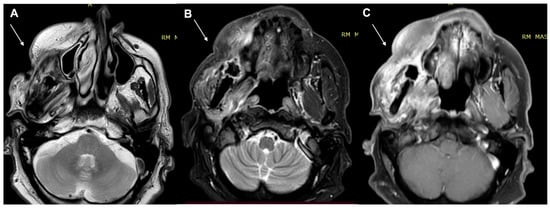

- Kawaguchi, M.; Kato, H.; Tomita, H.; Hara, A.; Suzui, N.; Miyazaki, T.; Matsuyama, K.; Seishima, M.; Matsuo, M. Magnetic Resonance Imaging Findings Differentiating Cutaneous Basal Cell Carcinoma from Squamous Cell Carcinoma in the Head and Neck Region. Korean J. Radiol. 2020, 21, 325–331. [Google Scholar] [CrossRef] [PubMed]

- Kawaguchi, M.; Kato, H.; Tomita, H.; Hara, A.; Suzui, N.; Miyazaki, T.; Matsuyama, K.; Seishima, M.; Matsuo, M. MR imaging findings for differentiating cutaneous malignant melanoma from squamous cell carcinoma. Eur. J. Radiol. 2020, 132, 109212. [Google Scholar] [CrossRef] [PubMed]

- Sheng, M.; Tang, M.; Lin, W.; Guo, L.; He, W.; Chen, W.; Li, K.; Liu, J.; Xiao, C.; Li, Y. The value of preoperative high-resolution MRI with microscopy coil for facial nonmelanoma skin cancers. Ski. Res. Technol. 2021, 27, 62–69. [Google Scholar] [CrossRef]